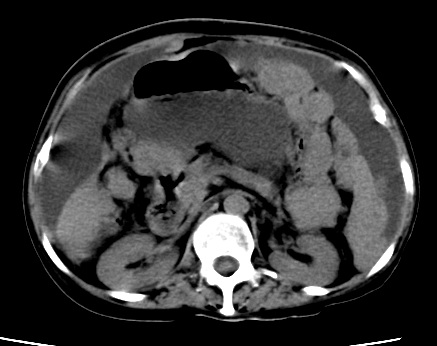

标题: CT23975:女61岁,腹部不适,明显消瘦

既往5年前卵巢癌行子宫及附件切除,右乳癌术后一年,考虑腹膜转移?

大量腹水,考虑腹膜转移。肝脏低密度灶。1囊肿,2转移。

1)结合病史,考虑腹膜及网膜转移瘤。2)肝脏多发性低密度灶,不排除转移瘤。3)大量腹水。

考虑卵巢癌行子宫术后复发,并肝、腹腔 、大网膜转移可能性大。

大量腹水。